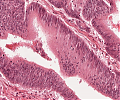

A70 Adenokarzinom des Kolon

Tumordrüsen mit deutlicher Kernpleomorphie

A70 Adenokarzinom des Kolon

Klein- und großdrüsige Tumordifferenzierung an der Invasionsfront